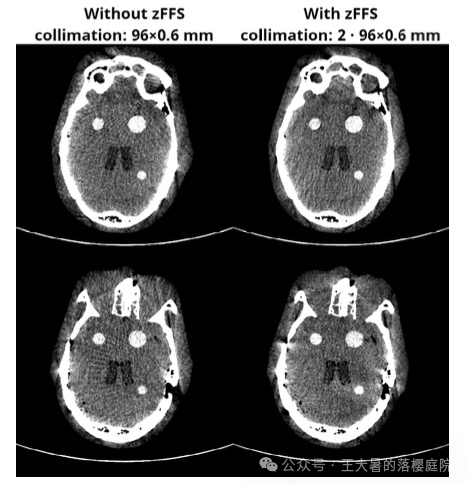

使用和不使用z轴飞焦点功能(z-flying focal spot ,zFFS)得到的图像如下图所示:

在RIDL网络的数据集的构造上,使用到了具有z轴飞焦点功能(z-flying focal spot ,zFFS)的CT扫描仪对数据集进行了构造。

如果将飞焦点技术应用到Z轴上,

即使焦点在Z轴方向上周期性运动(z-flying focal spot ,zFFS,在一些设备上被称为Z-Sharp技术),

能使同时采集的CT排数加倍,得到双倍于探测器数量的图像。